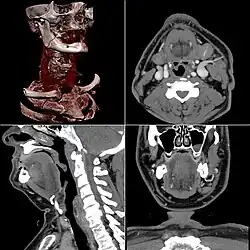

Computed tomography

Images generated from computed tomography, including a 3D rendered image at upper left

Computed tomography or CT scan (previously known as CAT scan, the "A" standing for "axial") uses ionizing radiation (x-ray radiation) in conjunction with a computer to create images of both soft and hard tissues. These images look as though the patient was sliced like bread (thus, "tomography" – "tomo" means "slice"). Though CT uses a higher amount of ionizing x-radiation than diagnostic x-rays (both utilising X-ray radiation), with advances in technology, levels of CT radiation dose and scan times have reduced.[9] CT exams are generally short, most lasting only as long as a breath-hold, Contrast agents are also often used, depending on the tissues needing to be seen. Radiographers perform these examinations, sometimes in conjunction with a radiologist (for instance, when a radiologist performs a CT-guided biopsy).